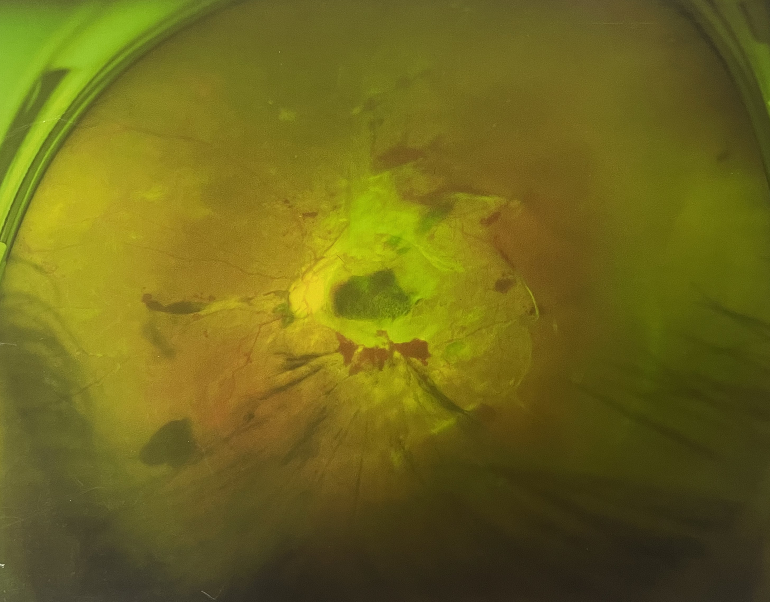

眼底出血一般多久能好?眼底出血可以由眼科本身疾病引起,常見的是視網(wǎng)膜靜脈阻塞、糖尿病視網(wǎng)膜病變、中心性滲出性視網(wǎng)膜病變、視網(wǎng)膜動脈硬化、老年性黃斑病變、視網(wǎng)膜靜脈周圍炎。

另外,眼底出血還可以由全身疾病引起,比如糖尿病可以引起眼底出血,高血壓也會引起眼底出血,還有嚴重的腎病,血液方面的疾病都可以導(dǎo)致眼底出血。

眼底出血一般多久能好?眼底出血是醫(yī)生用檢眼鏡才能看到,患者和其他人看不見。眼底出血不是單獨的病,一般來說是由眼科本身疾病造成,還可以由全身疾病造成。比如常見的視網(wǎng)膜靜脈阻塞、糖尿病視網(wǎng)膜病變等引起的眼底出血較常見。眼底出血一般多久能好?所以眼底出血的出血吸收時間也不一樣,要根據(jù)病情輕重決定其預(yù)后,出血吸收時間也不一樣。